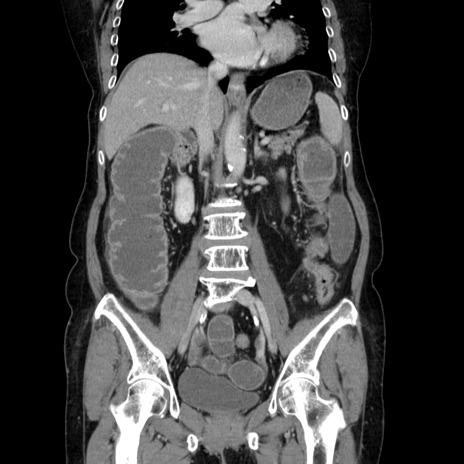

症例5(冠状断像)

【症例】70歳代女性

【主訴】お腹が張る

【現病歴】1週間くらい前から腹部膨満の自覚あり。昨日夜から増悪したため、本日救急外来受診。

【身体所見】意識清明、BT 36.5℃、BP 165/106mmHg、HR 80bpm、SpO2 98%、腹部:膨満、軟、自発痛・圧痛なし、触診にて不快感あり、腸蠕動音:減弱

【データ】WBC 12600、CRP 1.04